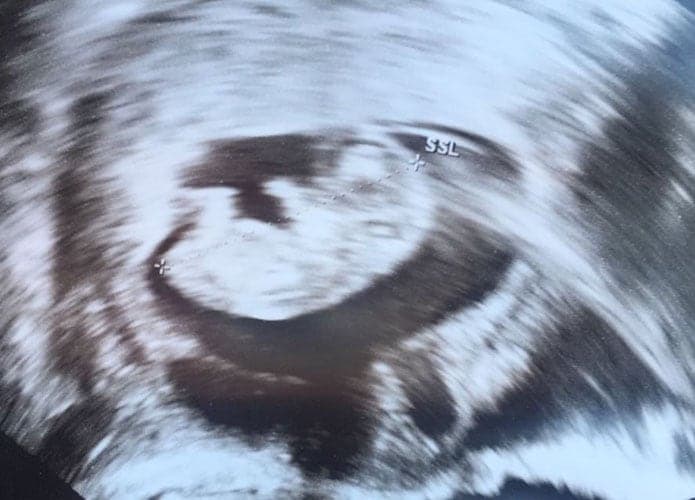

Ultraschallbilder aus dem 3. Trimester (29. bis 40. SSW)

Im dritten Trimester der Schwangerschaft ist das Baby so groß, dass es nicht mehr komplett auf ein Ultraschallbild passt. Nun kann man wunderbare 3D-Ultraschalle des Gesichts machen. In diesem Semester nehmen die Babys nochmal rasant zu und wer Glück hat, kann auf seinem Ultraschall schon erste Gesichtszüge erkennen.